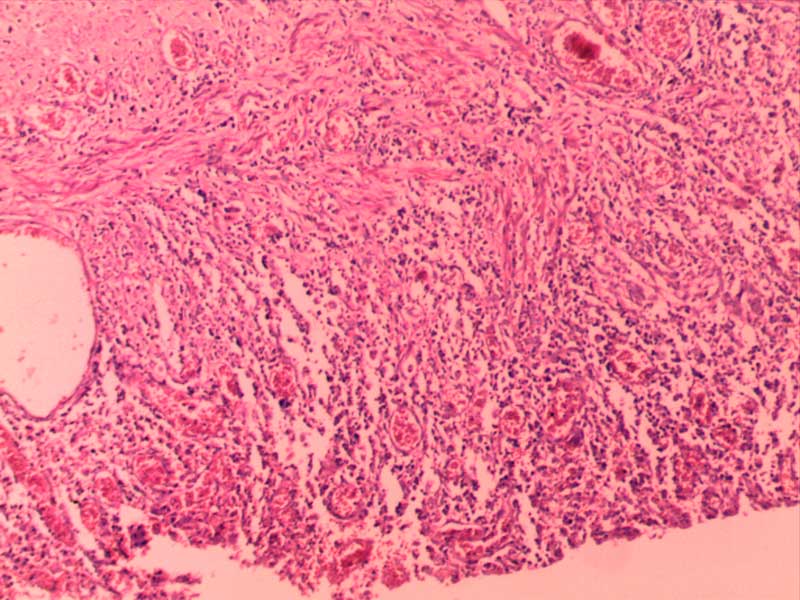

绒毛膜癌-10倍

肉芽组织-10倍

乳头状瘤(膀胱)4倍

乳腺癌-4倍

乳腺癌-10倍

神经鞘瘤4倍

神经鞘瘤-10倍-(2)

神经鞘瘤-10倍

大叶性肺炎(红肝期)10倍

大叶性肺炎(红肝期)-10倍

大叶性肺炎(灰肝期)-4倍

大叶性肺炎(灰肝期)-10倍